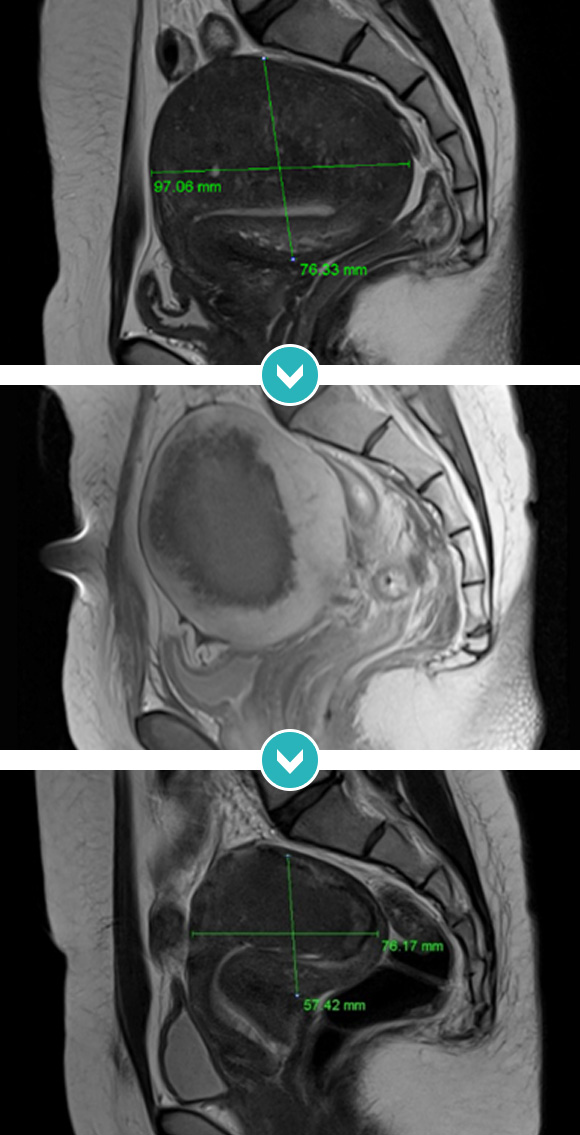

12cm 크기 자궁 전체적 자궁선근증 하이푸 치료후 80~90%이상 치료, 6개월 추적관찰